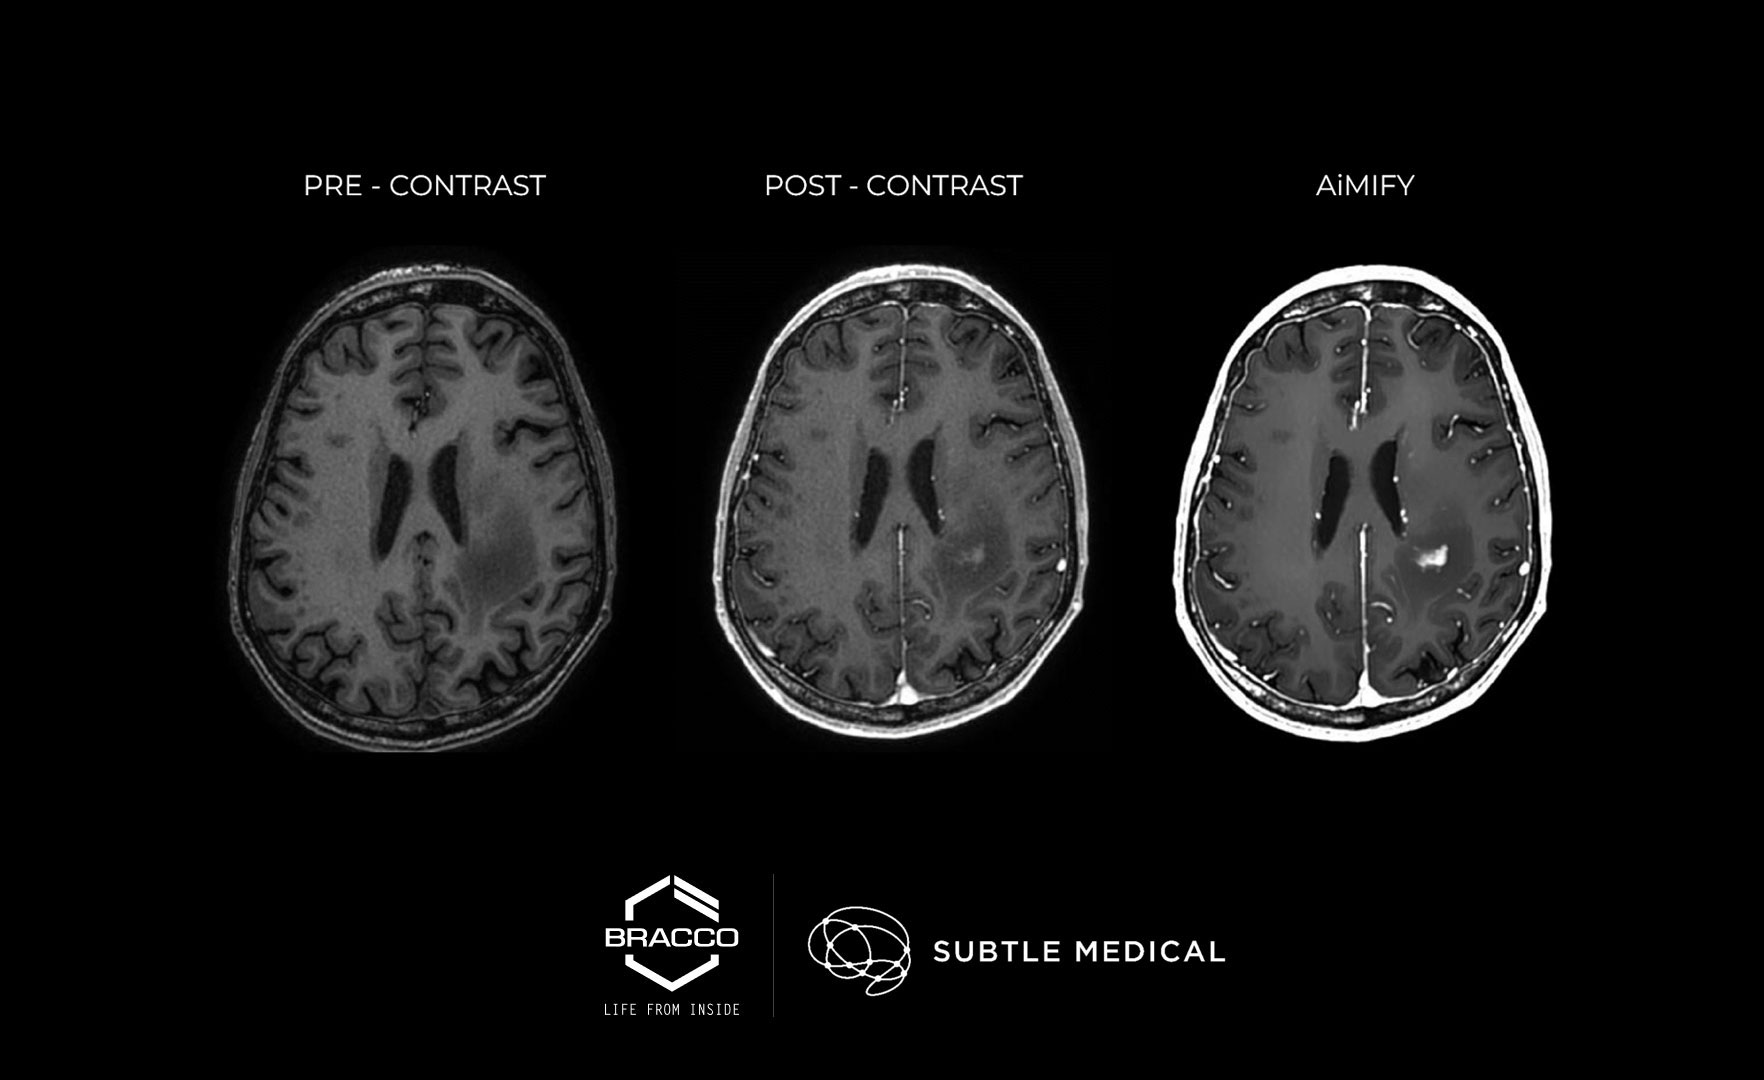

AiMIFY™ leverages advanced AI technology to amplify the contrast enhancement of brain MRI scans after administration of a labelled dose of Gadolinium-Based Contrast Agents (GBCAs) up to twice the initial value. This provides radiologists with improved contrast information - particularly aiding in the visualization of small and poorly enhanced lesions. AiMIFY™ has demonstrated consistent performance across a wide range of validation data, including diverse patient demographics, pathologies, lesion sizes, scanner vendors, MRI sequences, and acquisition orientations.